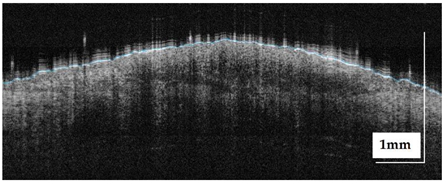

| Superficial spreading melanoma (SSM) Case 2 | Localization: right forefoot (right ankle) |

![]() | ![]() |